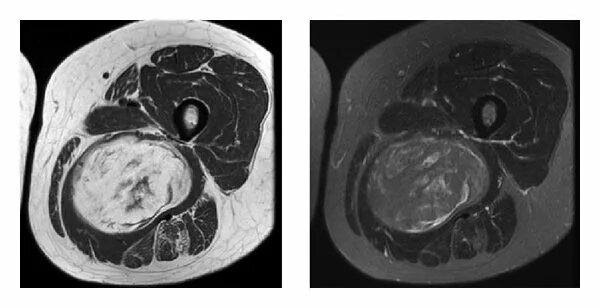

Кт тканей